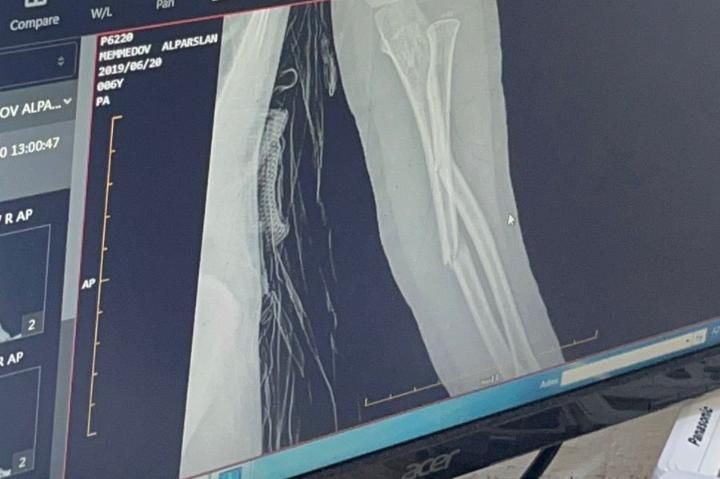

Hadisədən sonra Alparslanın rentgen müayinəsi zamanı bəlli olub ki, sol qolunda hər iki said sümüyünün 3/1 yerdəyişmiş sınığı aşkarlanıb. Travmatologiya İnstitunda ekspertizadan keçib, epikrizi var. Turanə Həmidova deyir ki, bağça müdirəsi övladının qolunun sınmasına biganə yanaşıb, onunla maraqlanmayıb: "Bağça müdirəsi övladının qolunun sınma saatını gizlətmək istəyib. Baş verən hadisənin videogörüntülərini əldə etmək istəyən valideynə yalnız yıxılma anının görüntüsü verilib.